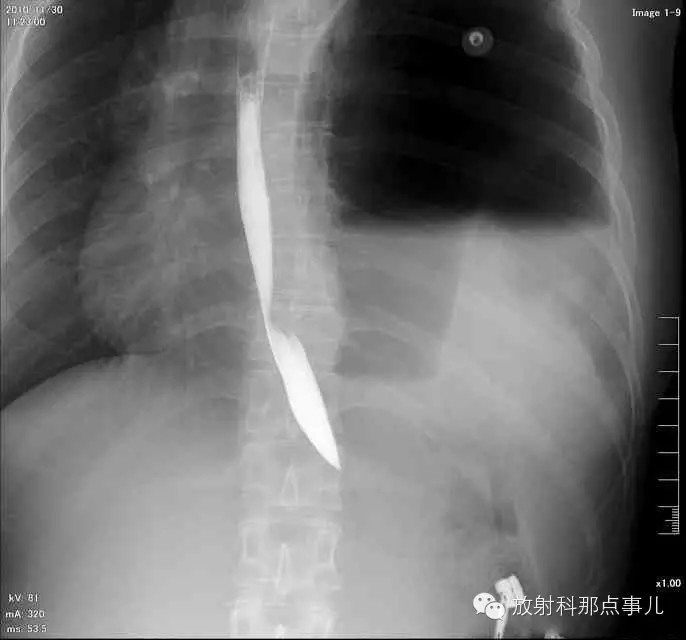

【病例学习】膈疝一例X线诊断

24岁,女性,腹痛渐加重并呕吐。

患者系顺产后18天产妇,产后感觉腹部疼痛不适,自认为正常反应,近两日因胸闷、腹部疼痛加剧伴呕吐来院就诊。

门诊腹部透视发现左侧胸腔巨大气液平面,为排除膈疝口服钡剂,但造影剂未见进入胃内。嘱住院,外科给予胃肠减压、补液等处理常规处理(未引流出明显气、液体)。5个半小时后再次检查,见少量造影剂进入消化道;为进一步了解情况,予泛影葡胺分别经胃管推注及口服,但均未进入胃内。当天进行外科急诊手术。

大部分胃、脾及横结肠均经过胸肋三角疝入左侧胸腔内,并见疝环形成。

考虑该患者因生产过程中腹压急剧升高,导致腹内脏器经膈肌缺损或薄弱部位进入胸腔内。